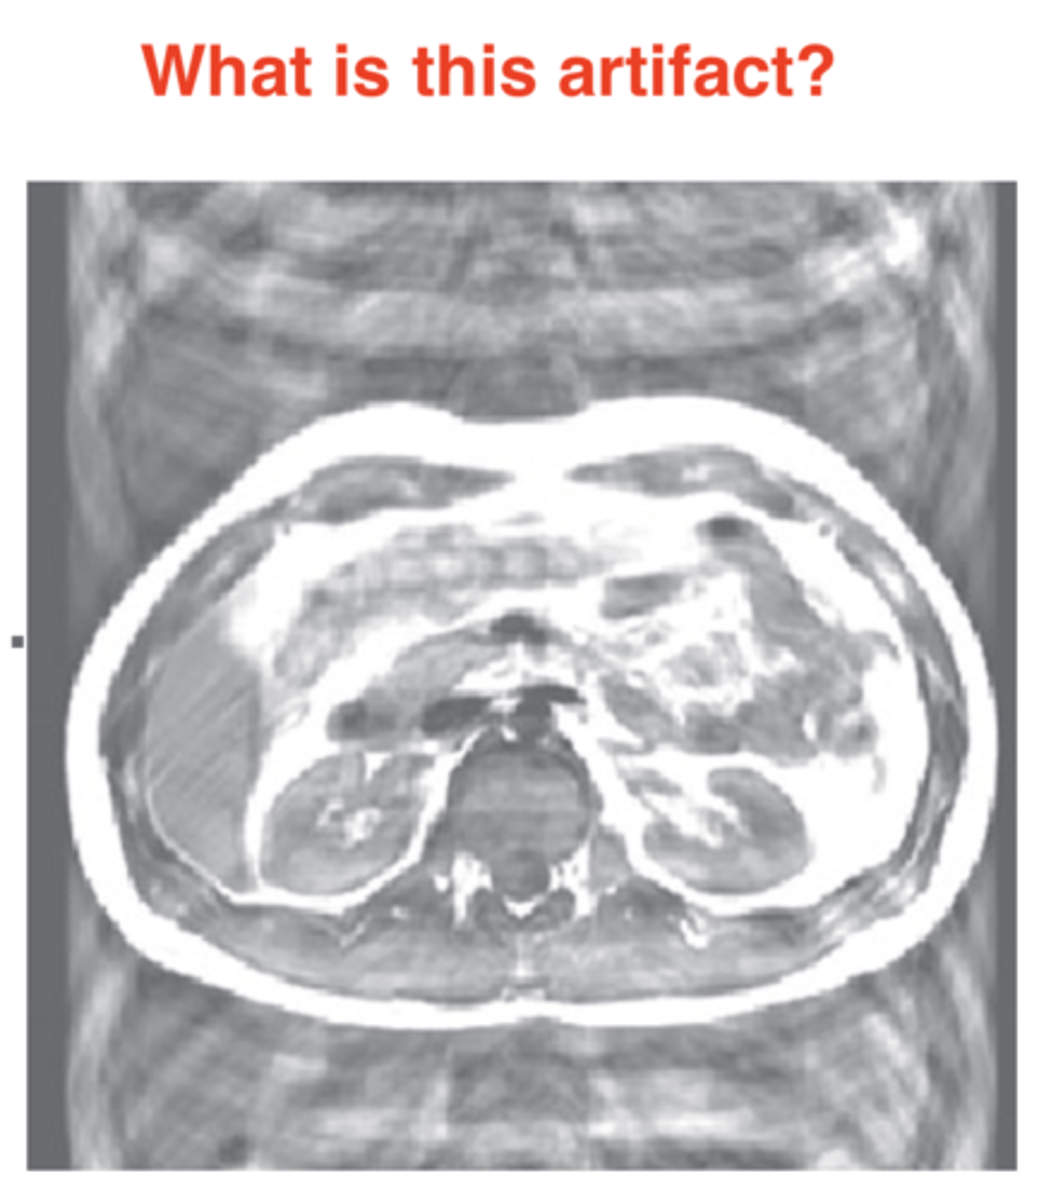

Aliasing/Wrap Artifact